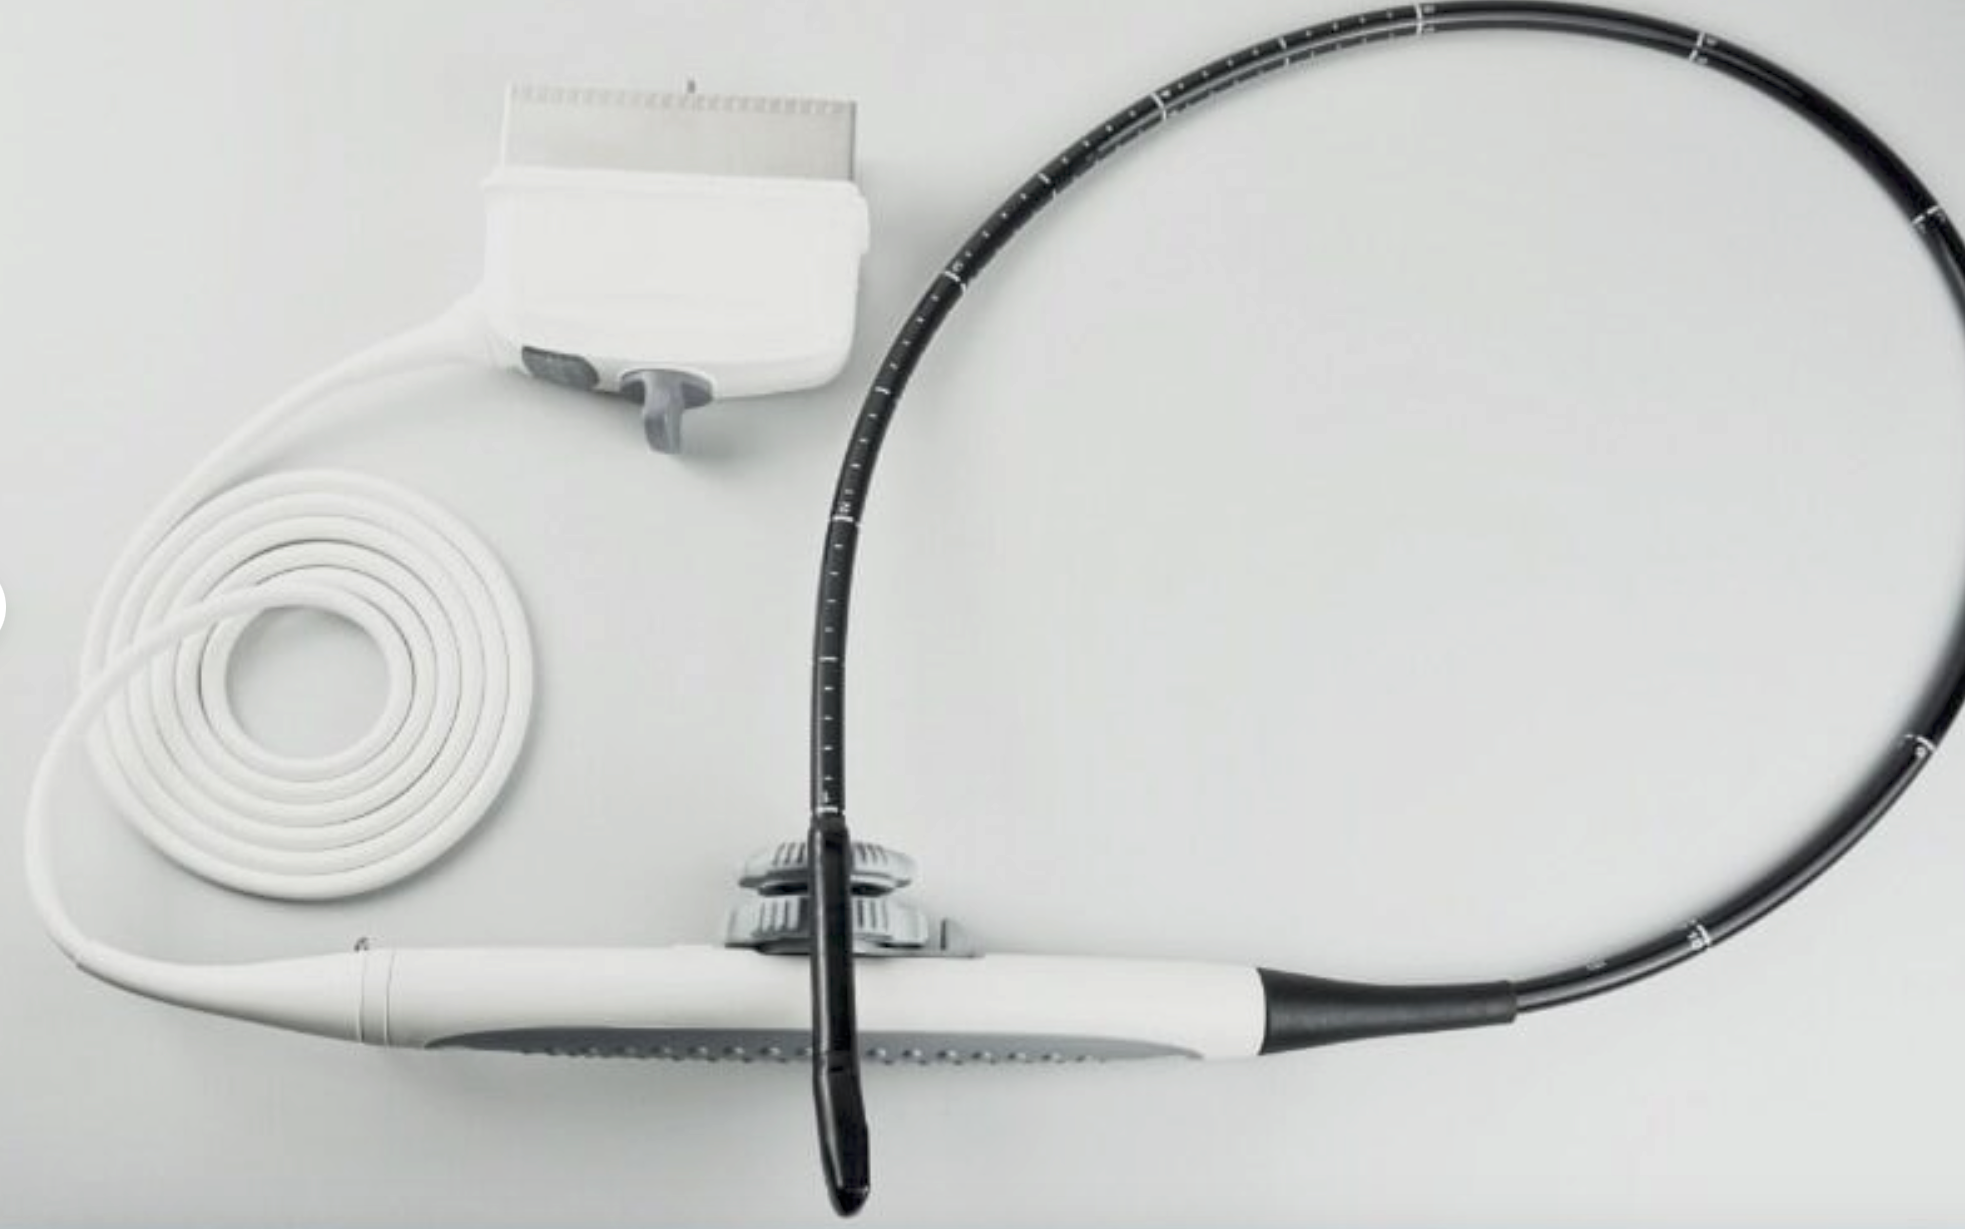

Probe Function: 3.5MHZ convex, abdominal organs

Probe 2: 7.5MHZ Transvaginal probe:gynecologic examination

The Diagnostic Ultrasound Scanner stands out for its exceptional imaging capabilities. Utilizing advanced digital technology, it provides clear and precise images, essential for accurate diagnostics. This scanner is equipped with both convex and transvaginal probes, allowing healthcare professionals to perform a wide range of examinations. Because of this versatile functionality, it greatly enhances the diagnostic process in various medical fields.